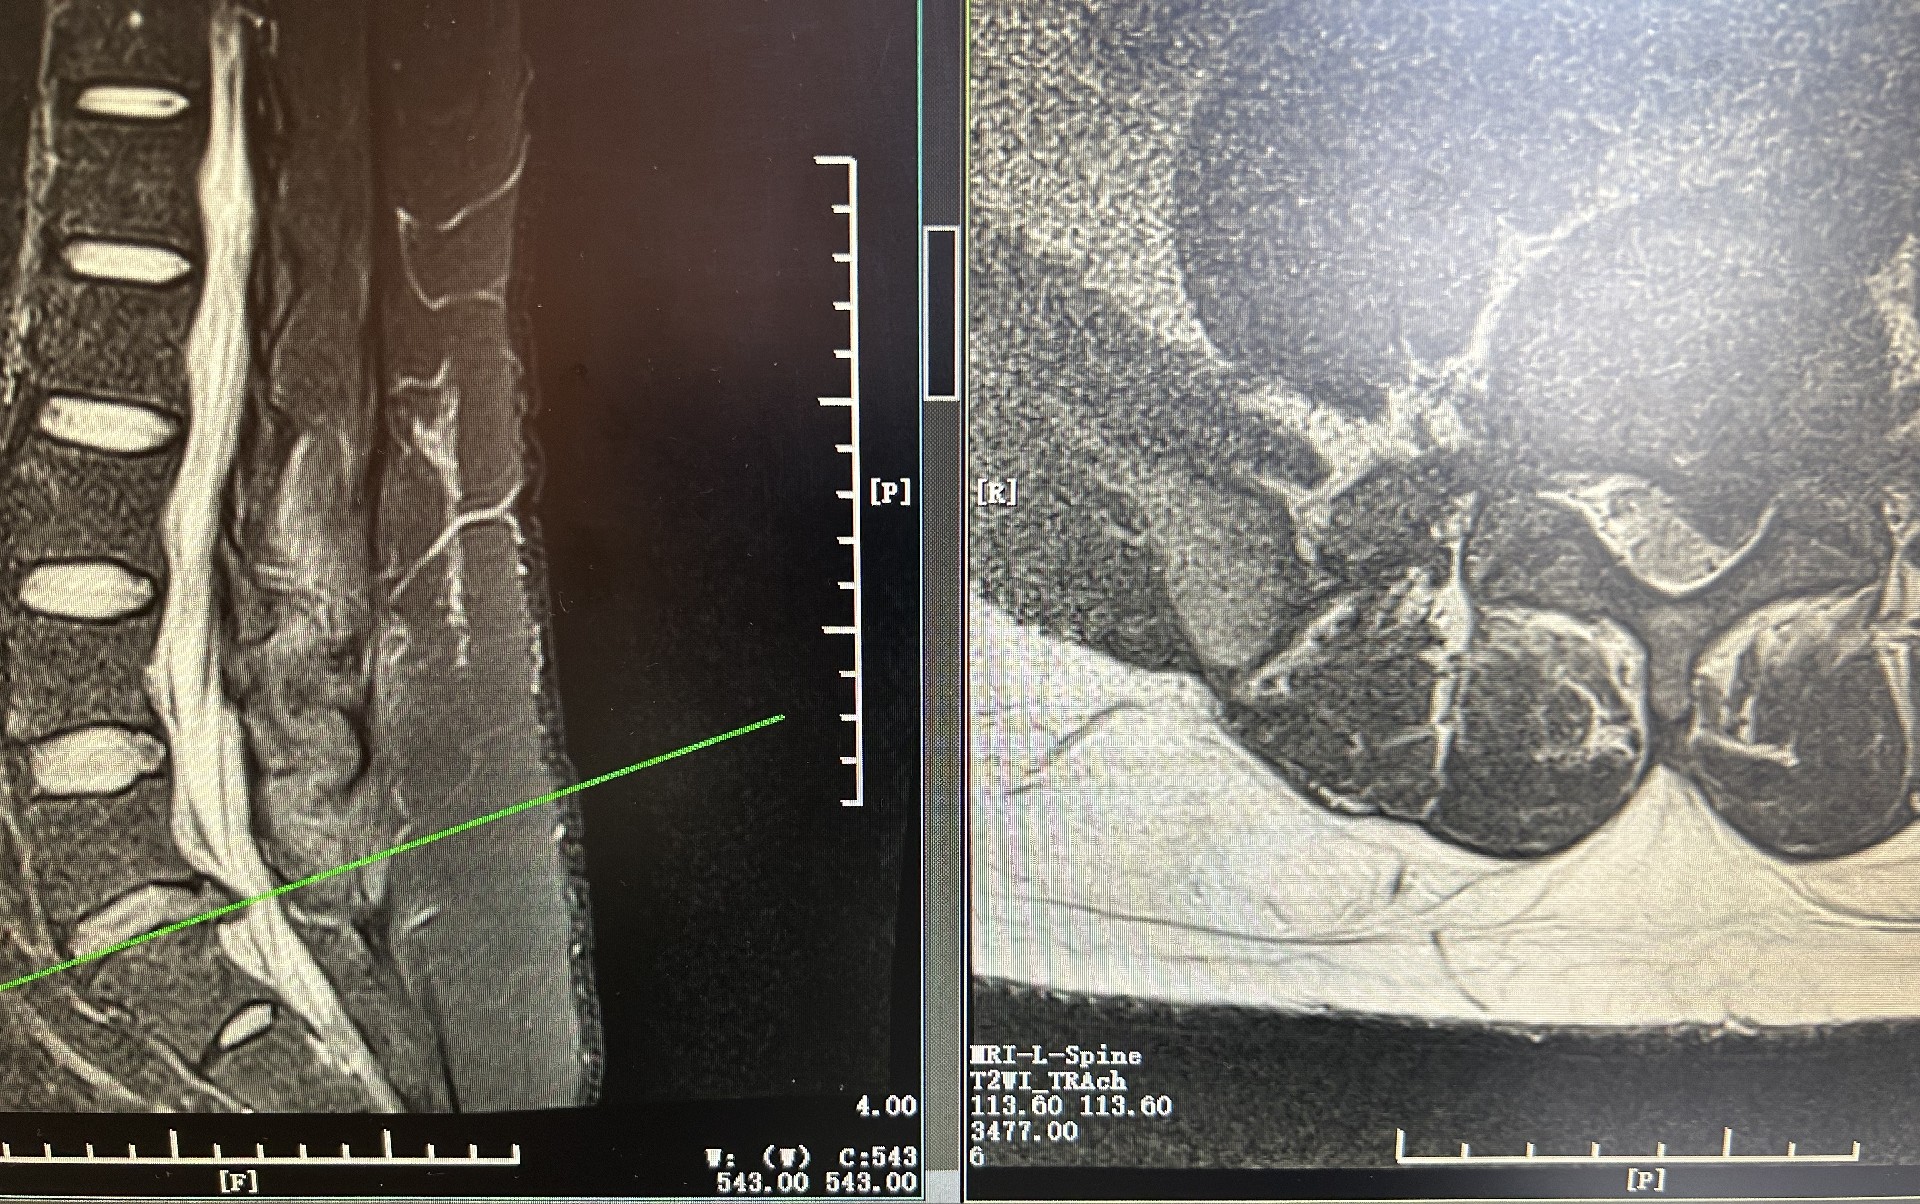

现代社会生活节奏较快,容易养成不良的生活习惯,腰椎间盘突出等脊椎疾病高发,严重影响着患者生活质量。在我院骨科诊疗中心,时常会遇见被疼痛困扰的患者。UBE脊柱内镜手术作为一种创新的手术技术治疗手段,受到了广泛关注。

UBE 技术的核心优势 视野开阔,精准定位病灶:借助UBE内镜,手术视野空间大,移动范围广,能清晰呈现椎管内的解剖结构,帮助医生精准定位病灶; 操作灵活,手术效率高:采用观察与操作两个独立通道,操作器械不受尺寸限制,医生可灵活运用,在各种脊柱微创技术中效率突出,缩短手术时间; 微创高效,术后恢复快:借助天然解剖间隙建立工作通道,对椎旁肌肉损伤较小,借助常规器械即可完成手术; 适应症广泛:能轻松完成镜下融合、颈椎、胸椎、腰椎等复杂病例,解决多种脊柱难题,适用人群更广泛。

开展各项脊柱专科手术:椎体爆裂性骨折伴(不)全瘫痪、腰椎间盘突出症、颈髓损伤、椎管狭窄及马尾神经损伤等重大脊柱疾病的手术治疗;腰椎间盘突出症的微创治疗,率先开展腰椎间盘突出症椎间孔镜下微创手术治疗技术,经皮椎体成形微创手术治疗,治疗老年椎体压缩骨折伴骨质疏松;各型四肢骨折钢板螺钉内固定术、微创髓内固钉内固定术、Liss钢板内固定术、股骨转子间骨折PFNA内固定术;股骨头坏死、先天性髋关节发育不良的保髋与关节置换等手术治疗;开展人工全髋关节置换术、全膝关节置换术等关节置换术、骨盆骨折等。